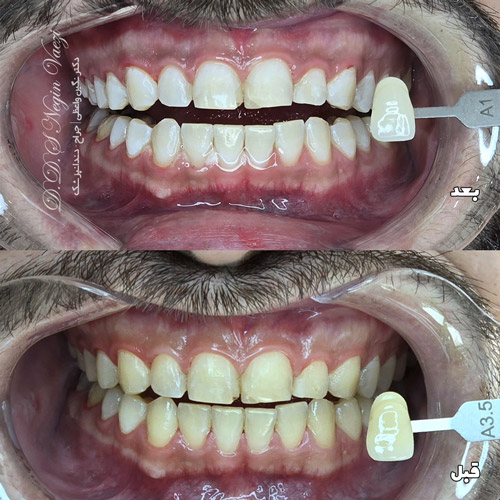

عکس قبل و بعد بلیچینگ دندان رو در این صفحه قرار دادیم تا شما نتایج واقعی سفید کردن فوری و موثر دندان با بلیچینگ رو مشاهده کنید. سفید کردن فوری دندان با روش های ایمن، بدون حساسیت و آسیب به مینای دندان، در یک جلسه انجام شده و نتیجه ای طبیعی و درخشان به همراه دارد. این نمونه کار قبل و بعد از بلیچینگ دندان که توسط دکتر نگین واعظی در مطب ولیعصر تبریز انجام شده است، با هدف کمک به شما در انتخاب بهترین روش سفید کردن دندان تهیه شده است.

جزییات عکس قبل و بعد بلیچینگ دندان

در این عکس قبل و بعد بلیچینگ دندان ، مشاهده میکنید که چگونه درمان بلیچینگ فوری در مطب ما در تبریز، در عرض تنها یک جلسه، دندان ها را تا 3 درجه روشن تر کرده است. تصاویر «قبل و بعد» بهطور واضح نشان میدهند که دندان ها بدون ایجاد حساسیت یا آسیب، سفید و درخشنده شده اند. استفاده از ابزار دقیق رنگ سنجی (Shade Guide) تضمین می کند که هر تغییر رنگ دقیقاً ثبت و قابل بررسی است.البته در این نمونه کار انقدر تفاوت رنگ مشهود است که نیازی به استفاده از shade guide نیز نشد.